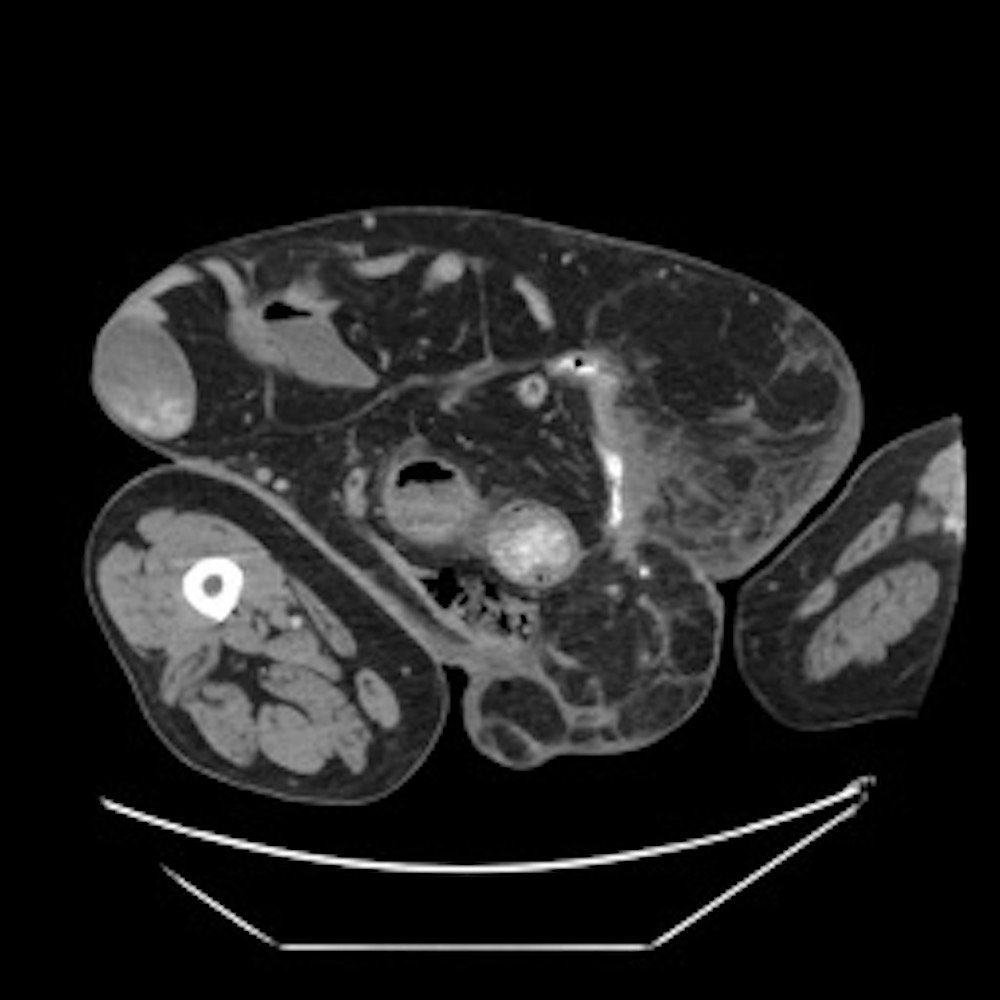

Computed tomography (CT) scan with intravenous (IV) contrast of the abdomen and pelvis demonstrated a large pannus containing a ventral hernia with abdominal contents extending below the knees (white circle), elongation of mesenteric vessels to accommodate abdominal contents outside of the abdomen (white arrow) and air fluid levels (white arrow) indicating a small bowel obstruction.